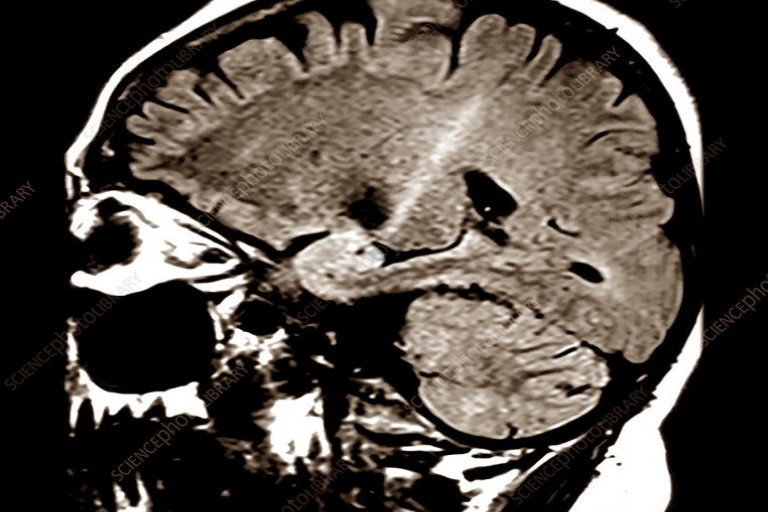

พบได้ทุกเพศ-วัย ในแสนคนจะพบ 4-6 ราย พบบ่อยในวัย 40-60 ปี เพศชายพบบ่อยกว่าหญิง ส่วนใหญ่จะมีชีวิตหลังป่วยภายใน 3-4 ปี มีแค่ 10% ที่อยู่ได้ถึง 10 ปี ขณะการรักษาทำได้เพียงประคับประคองอาการเท่านั้น รวมทั้งยังไม่รู้สาเหตุของโรคจึงยังไม่มีวิธีป้องกัน นพ.สมศักดิ์ อรรฆศิลป์ อธิบดีกรมการแพทย์ เปิดเผยว่า "โรคกล้ามเนื้ออ่อนแรง" ซึ่งมีชื่อทางการแพทย์ว่า Amyotrophic Lateral Sclerosis หรือที่เรียกสั้นๆ "เอแอลเอส (ALS)" เป็นโรคทางระบบประสาทโดยตรง เกิดขึ้นจากเซลล์ระบบประสาทที่ควบคุมกล้ามเนื้อเสื่อม แก่และตายก่อนวัยอันควร มีอาการกล้ามเนื้ออ่อนแรง แขนขาลีบ มีการกระตุกเต้นของกล้ามเนื้อ กว่า 70% จะเริ่มเป็นที่บริเวณแขนขาข้างใดข้างหนึ่งก่อนจะลุกลามไปสู่กล้ามเนื้อส่วนอื่น เช่น กล้ามเนื้อการกลืน กล้ามเนื้อทางระบบหายใจ ส่งผลทำให้พูดไม่ได้ หรือหายใจเองไม่ได้ จึงต้องใช้เครื่องช่วยหายใจ และทานอาหารผ่านสายยาง โรคกล้ามเนื้ออ่อนแรงเกิดขึ้นได้กับทุกเพศทุกวัย ที่ผ่านมา พบผู้ป่วย 4 - 6 คนต่อประชากร 100,000 คน และจะมีโอกาสพบผู้ป่วยรายใหม่ได้ประมาณ 1-3 คน ต่อปี โดยโรคนี้มักจะเกิดในกลุ่มผู้ที่มีอายุระหว่าง 40 – 60 ปี และพบในเพศชายมากกว่าเพศหญิง ส่วนใหญ่ผู้ป่วยจะเสียชีวิตหลังเกิดอาการเพียง 3 - 4 ปี มีเพียงแค่ 10% เท่านั้น ที่สามารถมีชีวิตอยู่ได้นานสูงสุดถึง 10 ปี ปัจจุบันยังไม่มีวิธีการรักษาโรคนี้ให้หายขาด การรักษาทำได้เพียงบรรเทาอาการและประคับประคองเพื่อให้ผู้ป่วยอยู่ได้นานที่สุด นพ.ธนินทร์ เวชชาภินันท์ ผอ.สถาบันประสาทวิทยา กรมการแพทย์ กล่าวเพิ่มเติมว่า ผู้ป่วยโรคกล้ามเนื้ออ่อนแรง สามารถกลับไปรักษาตัวที่บ้านได้แต่ต้องกินยาตามแพทย์สั่งตลอดเวลา นอกจากนี้ ผู้ดูแลต้องพยายามให้ผู้ป่วยออกกำลังกาย ทำกิจกรรมสม่ำเสมอเพื่อไม่ให้กล้ามเนื้อลีบแบน เกิดแผลกดทับและการติดของข้อ พักผ่อนให้เพียงพอ ลดเครียด รับประทานอาหารที่อ่อนนุ่มและไม่ต้องเคี้ยวมากในกรณีที่มีปัญหาเรื่องการกลืน หลีกเลี่ยงออกกำลังกายที่หนักเกินไป และหลีกเลี่ยงรับหรือสัมผัสกับยาฆ่าแมลงหรือพวกโลหะหนักและรังสีรุนแรง ซึ่งจะกระตุ้นทำให้เซลเสื่อมสภาพและตาย นอกจากนี้ คนในครอบครัวและญาติต้องให้กำลังใจและอยู่เคียงข้างเพื่อให้ผู้ป่วยได้ใช้ชีวิตที่เหลืออยู่อย่างมีความสุขที่สุด เนื่องจากยังไม่ทราบสาเหตุการเกิดโรคที่แท้จริงทำให้ไม่สามารถป้องกันได้ แต่มีคำแนะนำด้วยวิธีการดังต่อไปนี้ ดูแลสุขภาพตนเองให้ดี ที่สำคัญออกกำลังกายสม่ำเสมอ รับประทานอาหารที่มีประโยชน์ หากสงสัยว่าจะเป็นโรคกล้ามเนื้ออ่อนแรง ให้รีบไปพบแพทย์เพื่อตรวจวินิจฉัยป้องกันไม่ให้โรคลุกลามต่อไป